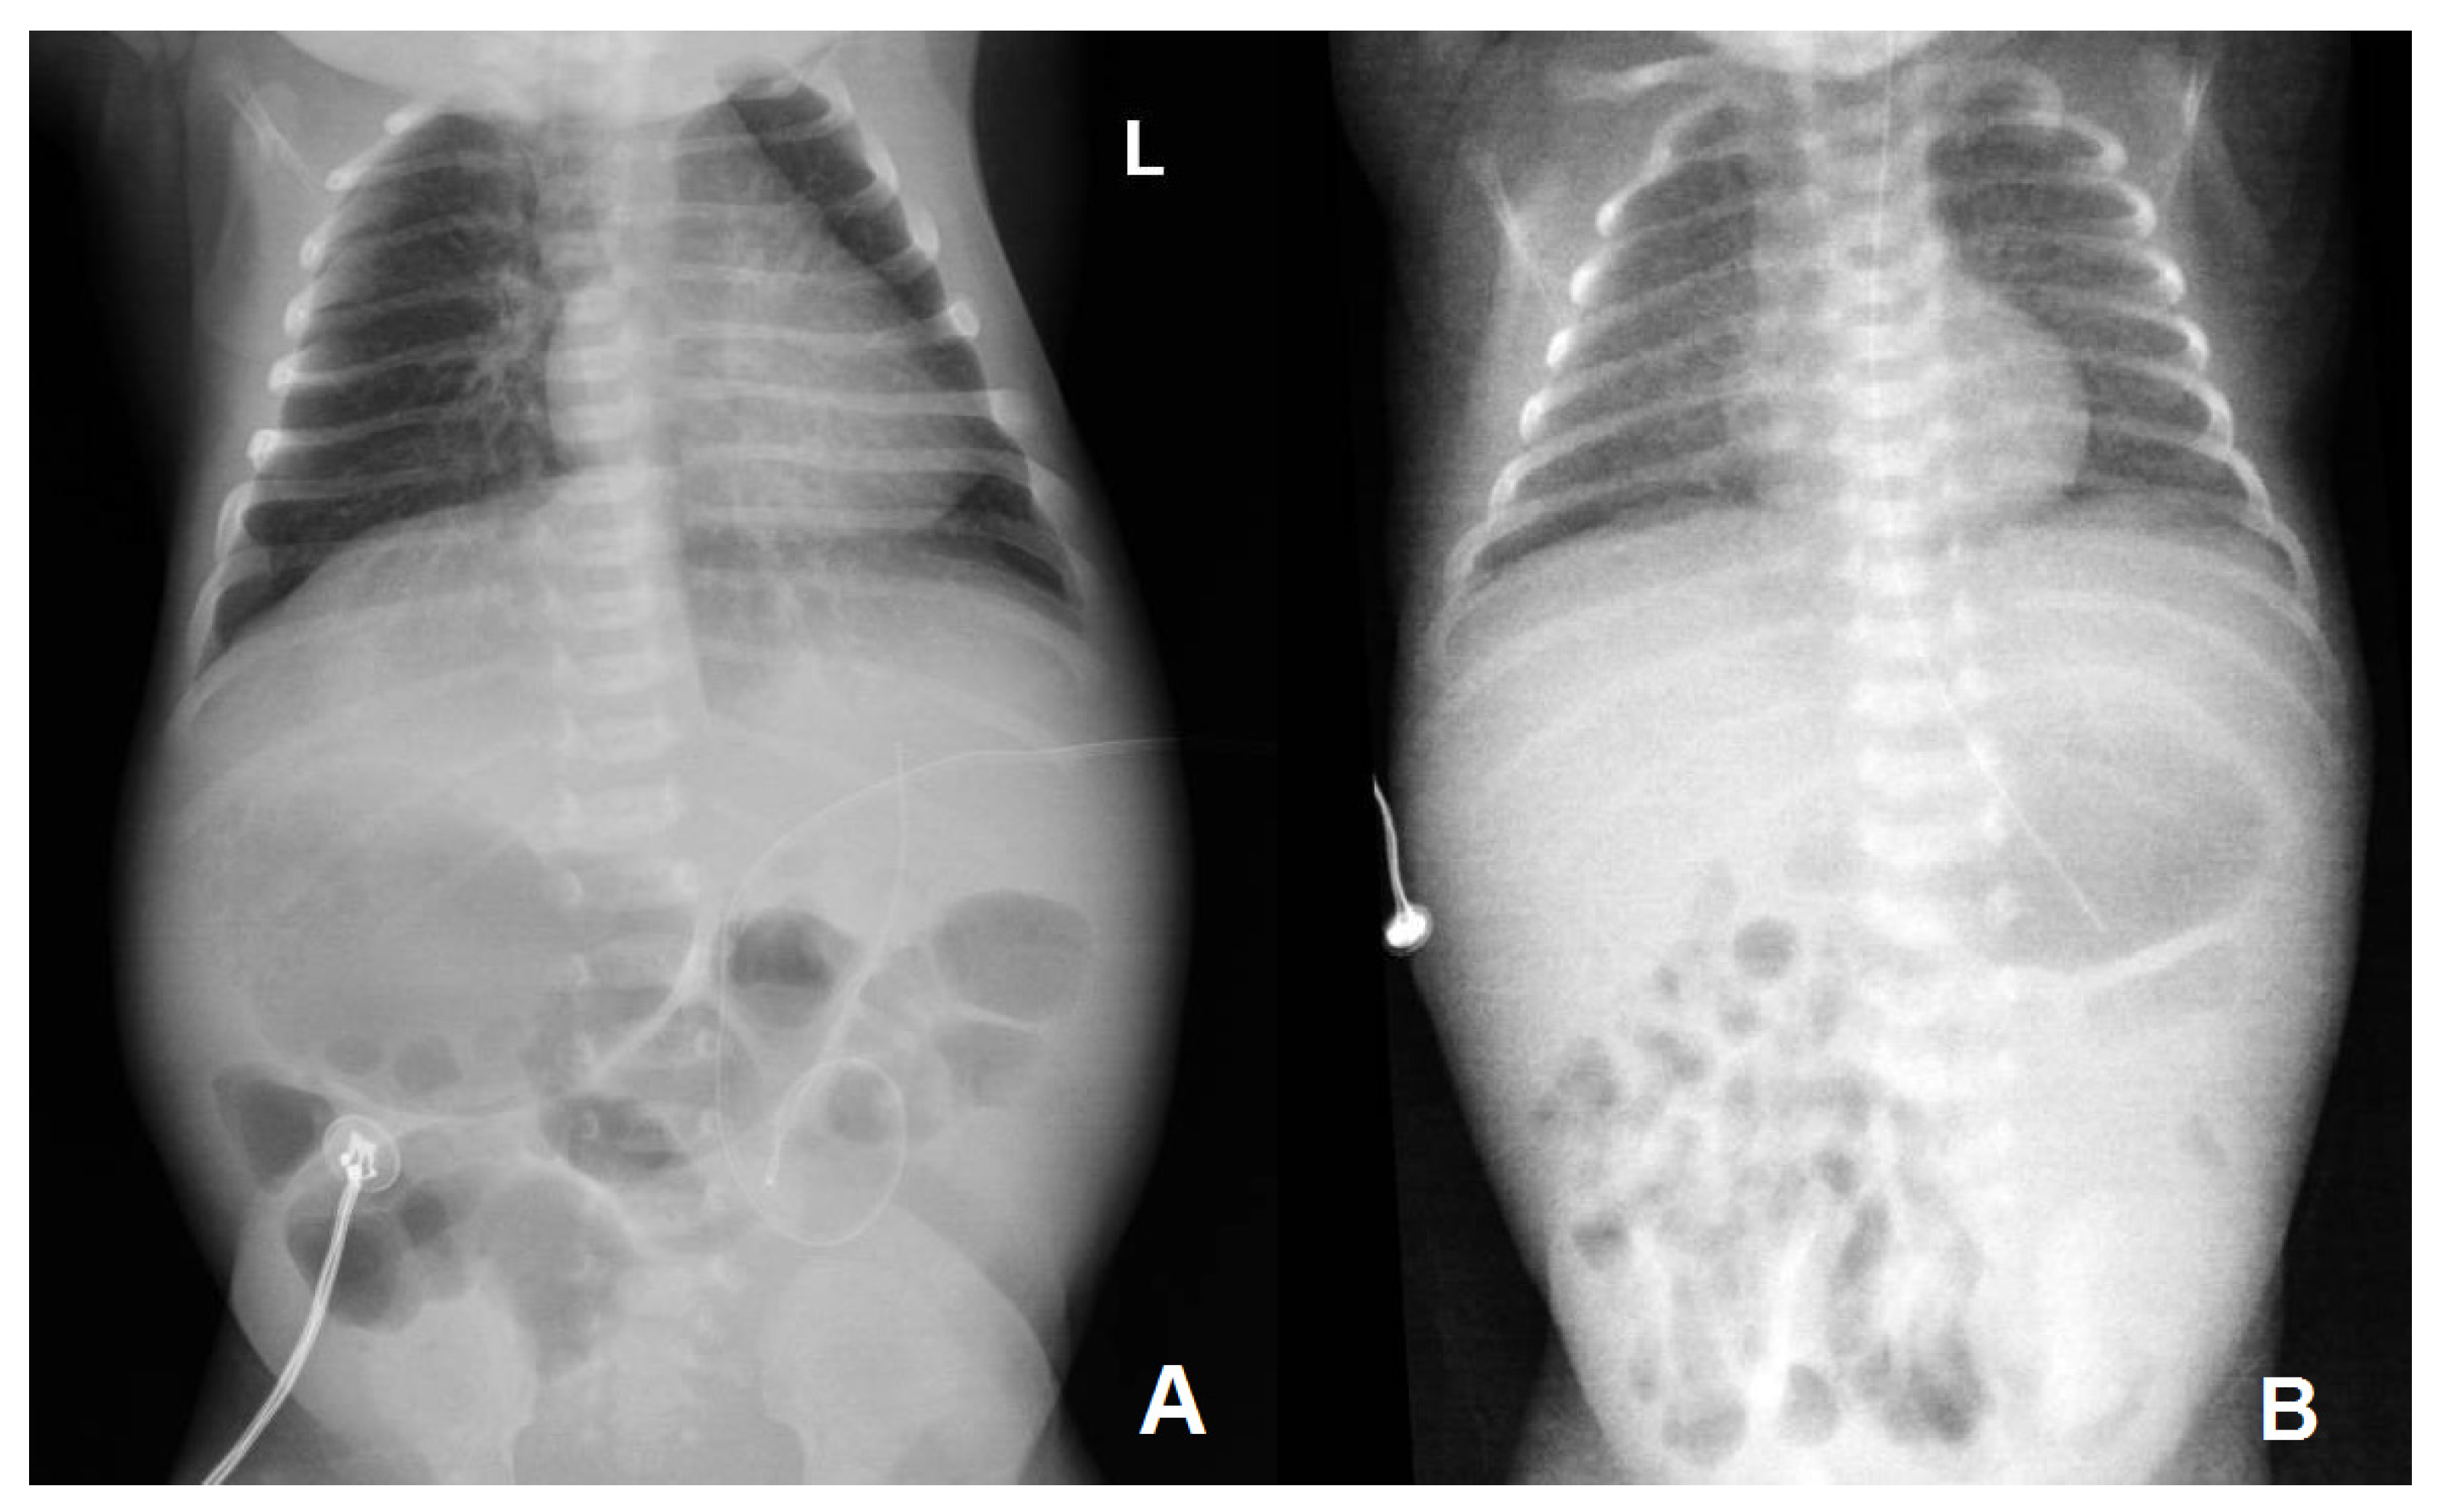

| Thoraco-abdominal radiography | No lung or abdominal involvement | Suggestive of respiratory distress syndrome due to surfactant deficiency on DOL 0; pronounced reticular, micronodular bilateral lung interstitium on DOL 5 | |||||||||||

| Abdominal ultrasound | Abdominal situs inversus on DOL 2; no abdominal parenchymal involvement on DOL 2 and 10 | Gross, inhomogenous, patchy echogenic areas disseminated, almost throughout the entire liver on DOL 9; fine granular echogenic areas limited to the fourth hepatic segment by DOL6 14; normal hepatic ultrasound structure on DOL 45 | |||||||||||

| Doppler echocardiography | Small PDA, PFO, right-sided aortic arch (DOL 1) | Small PDA, PFO on DOL 4 and 14 | |||||||||||